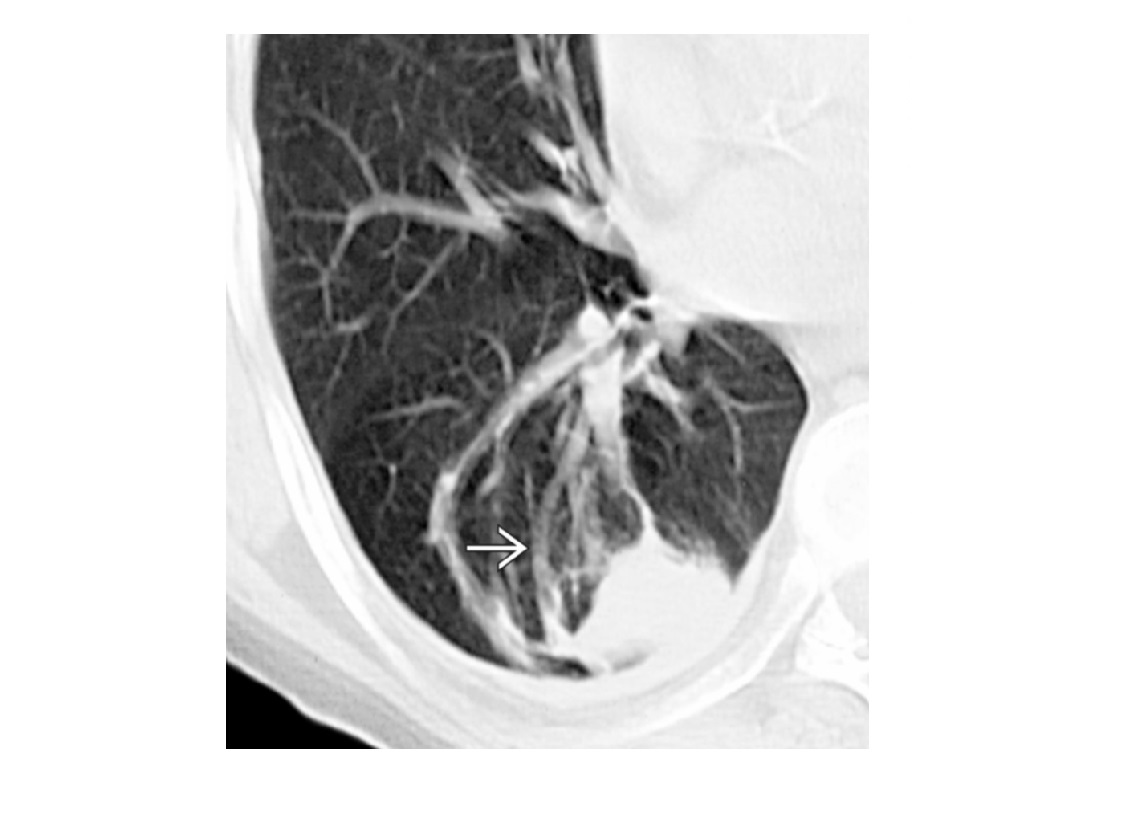

Higher attenuation pathological ie Parenchymal disease ie (GGO) - sarcoidosis, UIP, COP, DIP - No air trapping. =Vessels in the whiter areas = dilated Lower attenuation pathological **- look for vessels constricted/paucity in lucent areas ** 1. Poor ventilation = ***Air-trapping - Exacerbated by expiratory phase - Bronchitis , bronchiectasis, asthma, emphysema, Hypersensitivity pneumonitis 2. Mosaic perfusion - as above but no air trapping - CTEPH, pulmonary hypertension